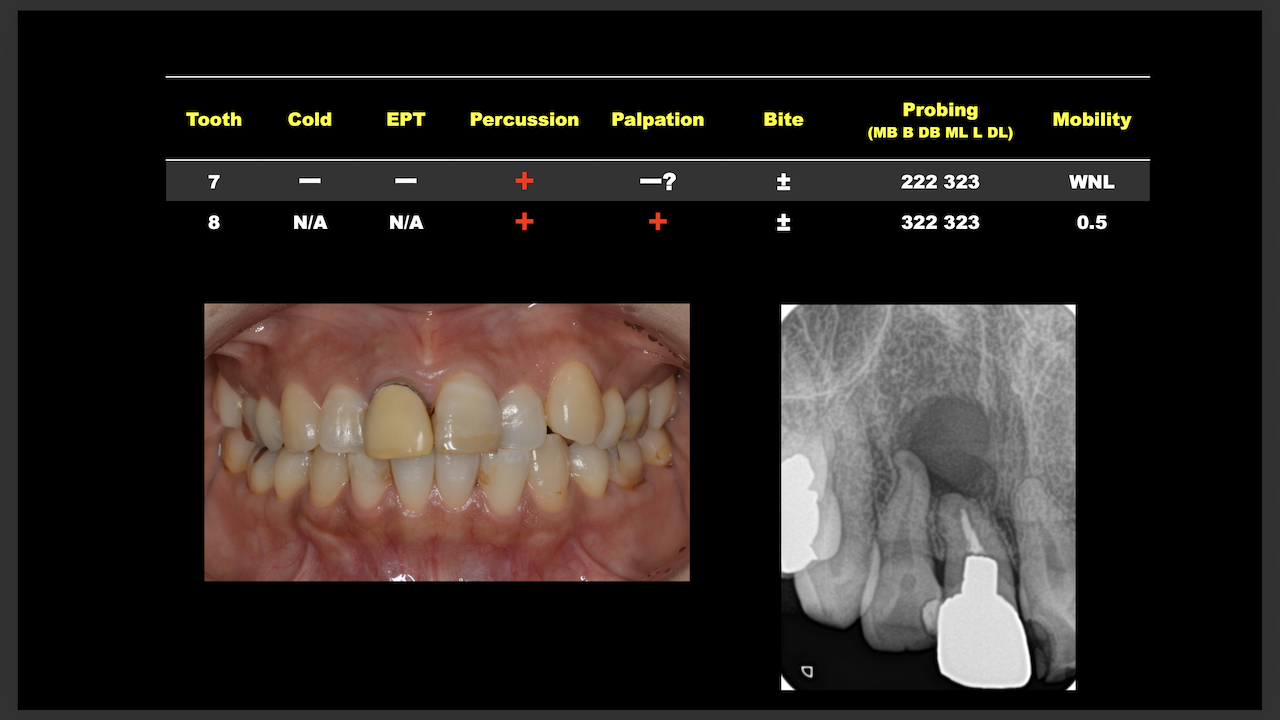

#7がCold testに無反応である。

故に、#7,8の非外科的根管治療を行うことになった。

が、#8のメタルコアは外しにくいだろう。

CBCTでは2本とも口蓋側の皮質骨が消失している。

という絶望的な状況である。